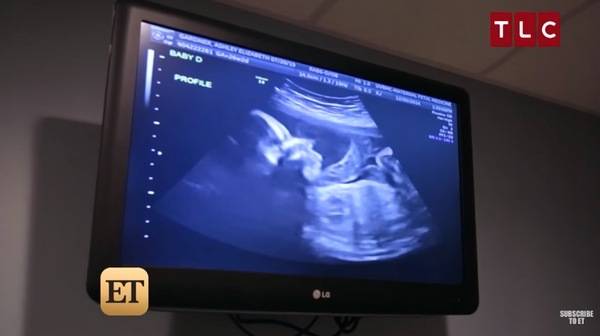

When Ashley and Tyson went for their first ultrasound, they expected – just like any other parent – to get a first look at their baby.

But when the pictures appeared on the screen, the doctors informed the couple that two fertilized eggs had split.

The couple did not look at one baby, or two, or three.. but at four! Ashley was pregnant with two sets of identical twins.

The chance of this happening is 1 in 70,000,000 – a miracle piece!